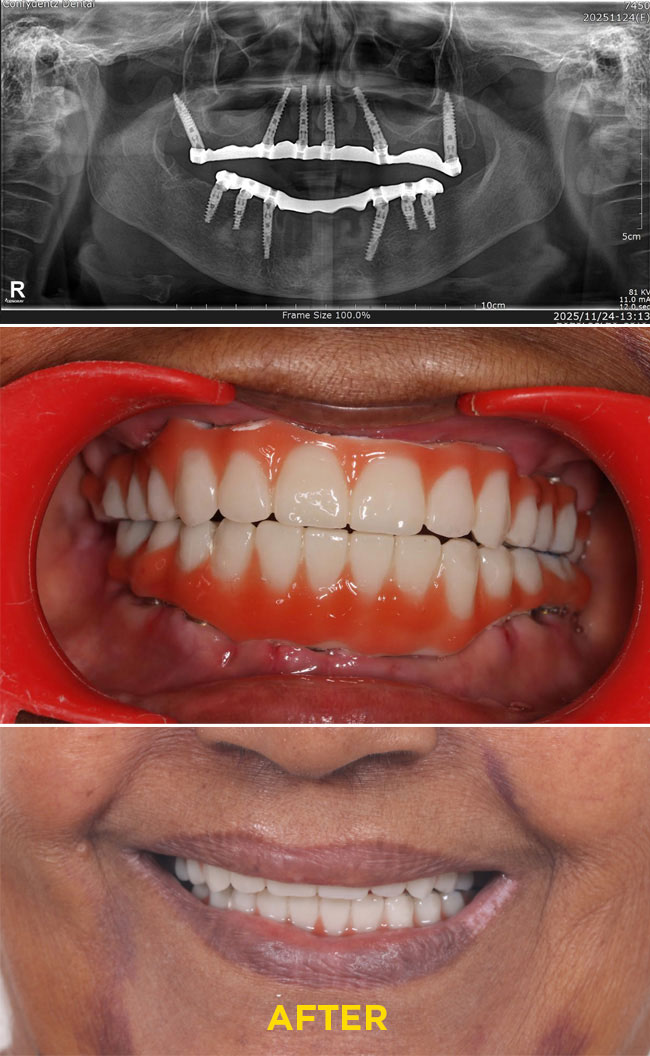

Case - 4